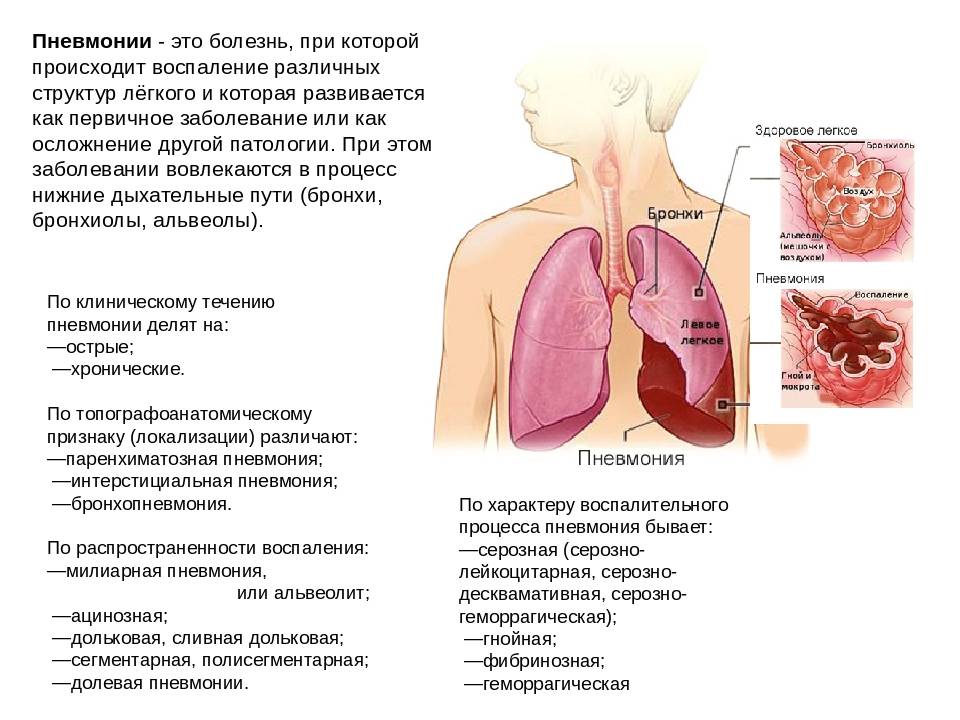

Медицинская тема: легочные осложнения при пневмонии